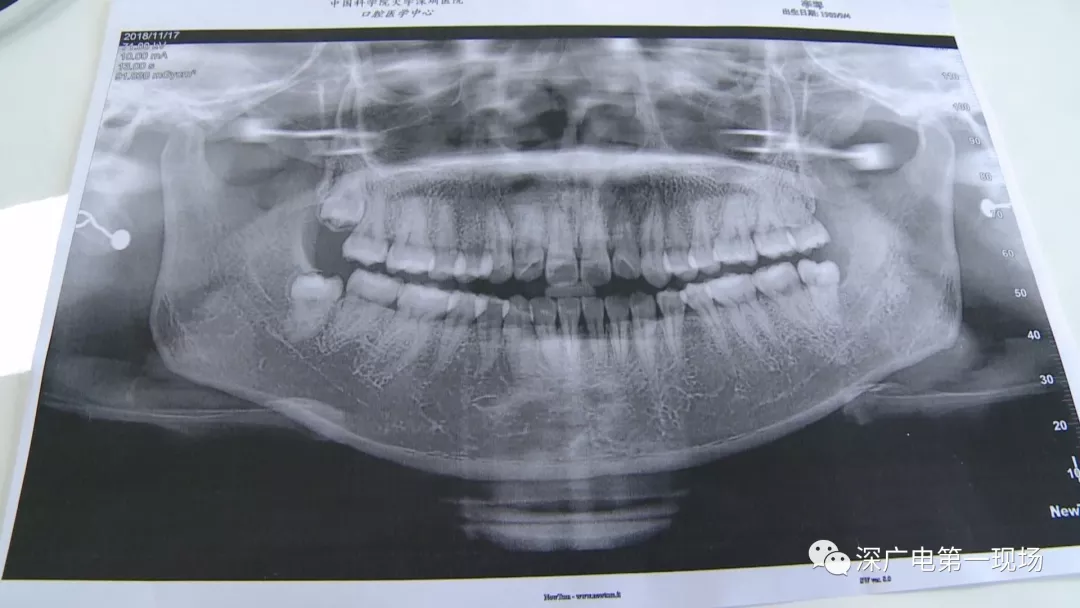

拔一顆智齒一千六?! 深圳這位女士默默的放下了賬單……

隨后,李女士在網(wǎng)上查詢,發(fā)現(xiàn)拔智齒的收費都是參差不齊,也沒有參考標(biāo)準(zhǔn)。在李女士提供的拔牙收費單上,記者注意到,除了一些拔牙必用的藥物外,還有一些輔助工具的費用。

聽聽醫(yī)生怎么說

中國科學(xué)院大學(xué)深圳醫(yī)院口腔科主任賈岳介紹,對于不同患者的牙齒,它的治療方法都不一樣,所以不同牙齒,醫(yī)院收費的標(biāo)準(zhǔn)也各不相同。牙齒的治療方案,都是根據(jù)患者牙齒具體情況來制定,然后再去收費,同時也會參考病人實際情況來做不同的治療項目。